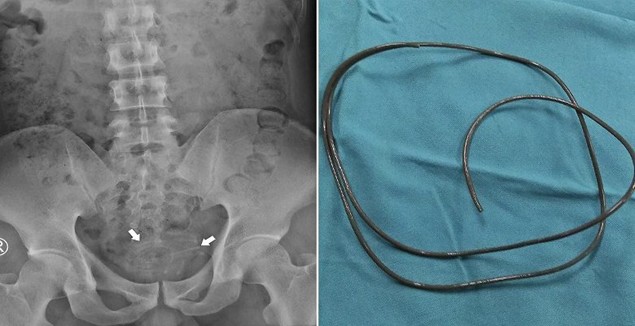

Le fil avait été enroulé et heureusement non attaché à la paroi de la vessie, avec une extraction réalisée à l’aide d’une pince à préhension, tandis que le fil de l’écouteur aurait une longueur de 80 cm.

L’étrange insertion a été réalisée « sur la base du plaisir et de la gratification s3xuelle », et le fil qui s’était logé dans sa vessie a été « visible et rapidement identifié » par l’équipe hospitalière.